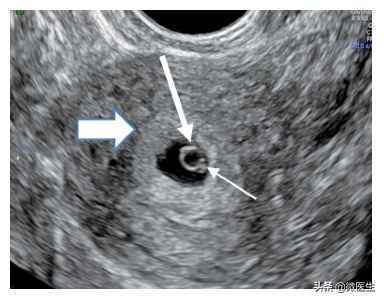

胚胎植入是试管婴儿成功的关键步骤,接受试管婴儿治疗的过程相当复杂;当受精卵成功发育成胚胎时,如何准确将胚胎顺利植回母体子宫腔内使之在子宫内膜成功着床,特别关键。专家说,胚胎植入需要靠胚胎技术员及临床医师的共同努力,没有健康的胚胎,胚胎植入必然会失败,同样的,如果胚胎植入时受到外伤,纵使胚胎技术员维持胚胎良好的状况也是无用的。因此若患者条件良好,拥有好的着床环境及顶级胚胎,可说已成功一半,要是能顺利完美的植入胚胎,则更接近成功。

专家指出,试管婴儿成功的四大基石是:完美的诱导卵巢排卵计划、质量良好的胚胎、良好的子宫内膜准备、完美的胚胎植入。一旦胚胎都已培养到完美的好胚胎,则一个完美的胚胎植入术,可以说试管婴儿成功的临门一脚,十分重要。但是很多时候,过程当中无法达到这么理想的状态。